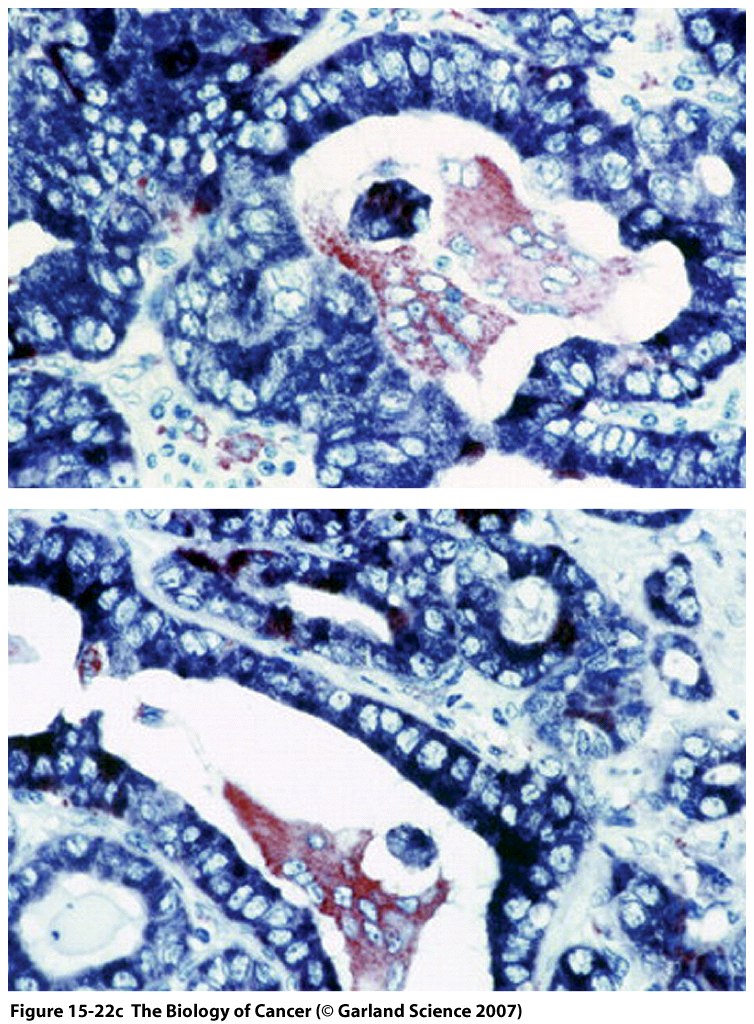

This Concept Map, created with IHMC CmapTools, has information related to: Section 15.11, immune recognition is delayed in tumors, adjuvants can activate macrophages, macrophages are part of immune recognition